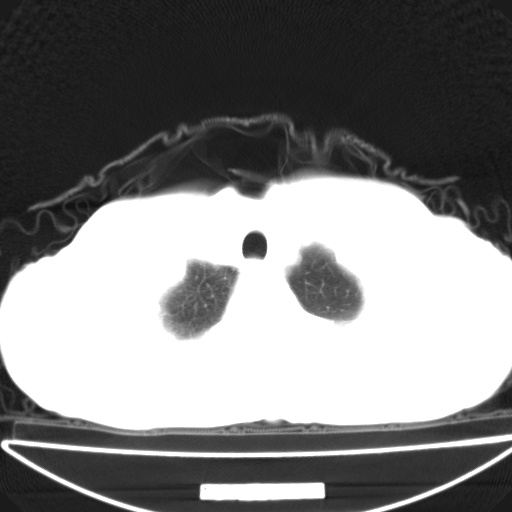

以下是引用jsgdoctor在2008-11-6 22:12:00的发言:[br]右主支气管壁明显增厚,管腔狭窄.考虑为右侧中央型肺癌伴阻塞性炎症\\肺脓肿.

以下是引用zjzjr在2008-11-6 20:25:00的发言:[br]中心型肺ca,合并阻塞性肺炎

以下是引用zsl6918在2008-11-6 19:43:00的发言:[br]右侧中心性肺癌(鳞癌)